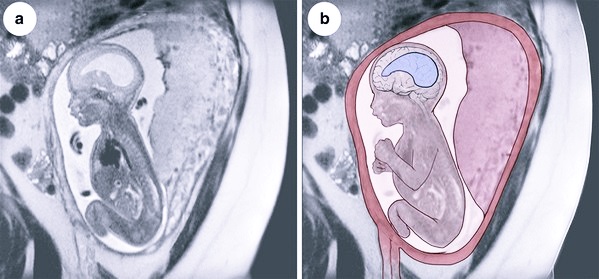

Анализ структур головного мозга у плода проводят во втором триместре, в период между 18 и 27 неделями беременности. В большинстве случаев патологические изменения обнаруживаются на плановом УЗИ. Диагноз также ставят на 30-33 недели беременности.

Приобретенная вентрикуломегалия у новорожденного диагностируется при комплексном обследовании. Лабораторные анализы, инструментальные исследования делают в рамках дифференциальной диагностики. Болезнь нужно отличить от гидроцефалии.

Показатели УЗИ, МРТ, проведенных до родов и после, в 57-83% случаев существенно отличаются. Если у плода обнаружили расширение желудочков, не стоит паниковать. Для подтверждения или опровержения диагноза необходимо пройти повторное ультразвуковое и томографическое обследование новорожденного. Такие доводы представлены в издании «Частота и причины расхождений диагностических изображений у детей с вентрикуломегалией» G. M. Senapati, 2010.